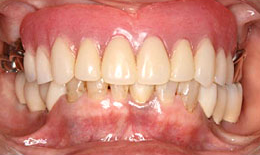

インプラント症例(2) 61歳 女性

治療方法

- 上顎

- 義歯を作製

- 下顎

- インプラントを5本埋め込み、セラミックスクラウンを被せた